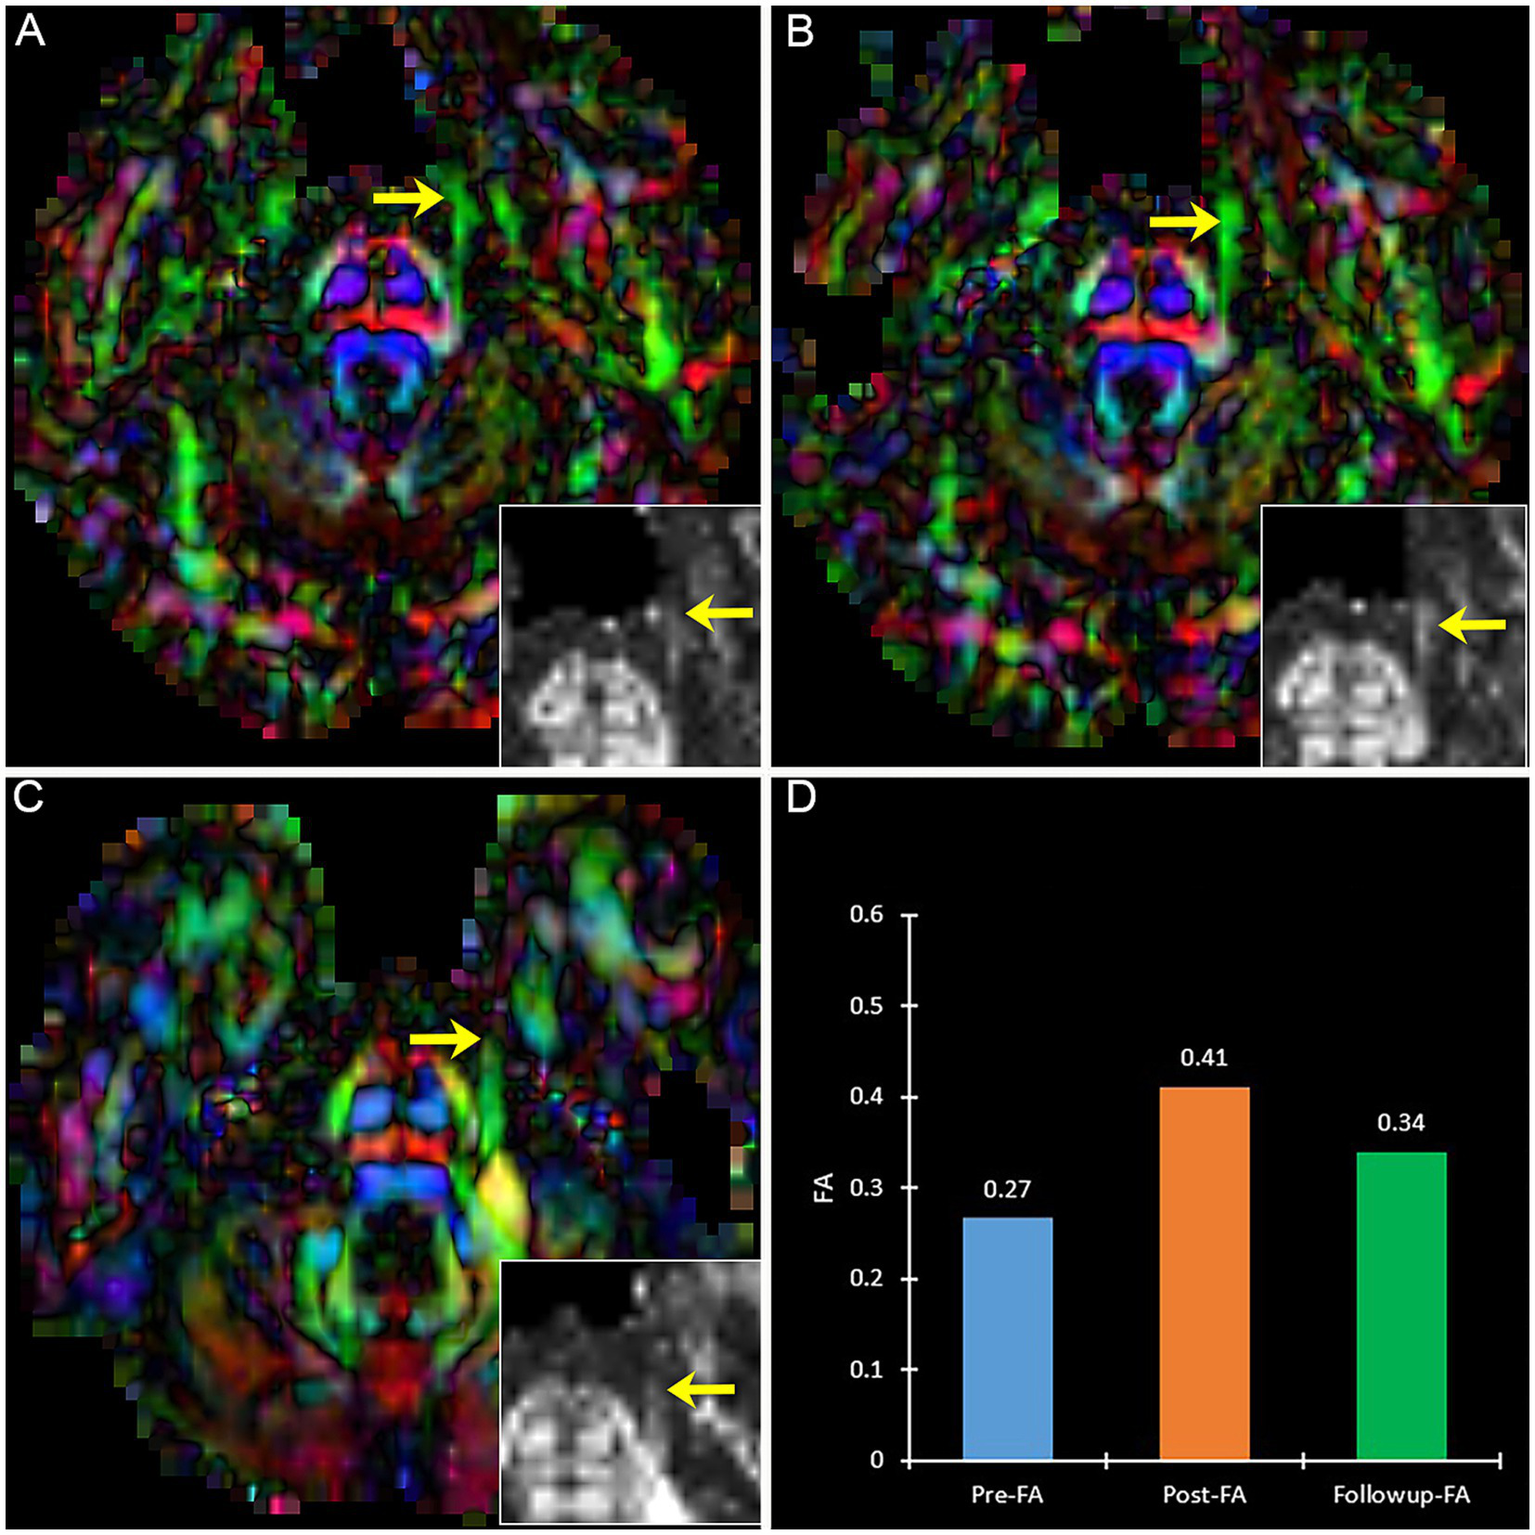

Figure 6

The DTI images (FA-color maps) of an effective patient after treatment in preoperative (A), postoperative (B), and follow-up (C). Image (D) shows the FA values on three-time points. (A–C) show the bilateral CNV tracts, and the insert box is the local FA map on the affected CNV. Yellow arrow: the affected CNV tract.

Figure 7

The DTI images (FA-color maps) of an ineffective patient after treatment in preoperative (A), postoperative (B), and follow-up (C). image (D) shows the FA values on three-time points. (A–C) show the bilateral CNV tracts, and the insert box is the local FA map on the affected CNV. Yellow arrow: the affected CNV tract.

A patient with effective PSR treatment (Figure 6) manifests an increased trend of FA after treatment. Contrary to effective patients, a patient with ineffective PSR treatment in follow-up manifests a decreased trend of FA (Figure 7).

By analyzing the VAS scores and diffusivity metrics of TN patients before and after treatment, we found that the diffusivity metrics (FA) and the VAS scores all changed at the same time (Figure 8). The alteration of the diffusivity metrics FA and the change of VAS scores are consistent in most patients (71.4%, 10/14). The diffusivity metric (FA) on the lowest FA area of the CNV preoperative is significantly negatively correlated with the VAS scores (Coefficient of correlation = −0.66, p < 0.05).

At follow-up, VAS further decreased to 0–2 after a 6-month follow-up in 11 patients, and others with VAS of 3–7 (Patient 8, 10, 11, and 12) (Figure 8). Five patients underwent DTI at the 3-6th month follow-up. Four patients had further FA increases compared with preoperative values, ranging from 24.7 to 103.8%. One recurrent patient (Patient 11) experienced a decrease in their FA value on TG by 26.6% when compared to their 3-day postoperative FA value (Figure 8). At 18 - month follow - up, there were still only four patients with recurrence, and the VAS of these recurrence patients was 7, 4, 4, and 2 (Figure 8).